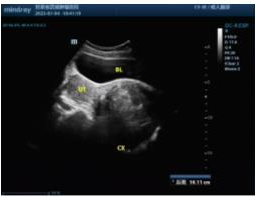

手术前我们再次确认患者的HPV检测阴性;宫颈TCT涂片:无上皮内病变或恶性病变(NILM)。血常规、肝功能、肾功能、心功能、肺功能等均无明显异常。B超、核磁共振检查(如下图)。

2023-7 经阴道彩超